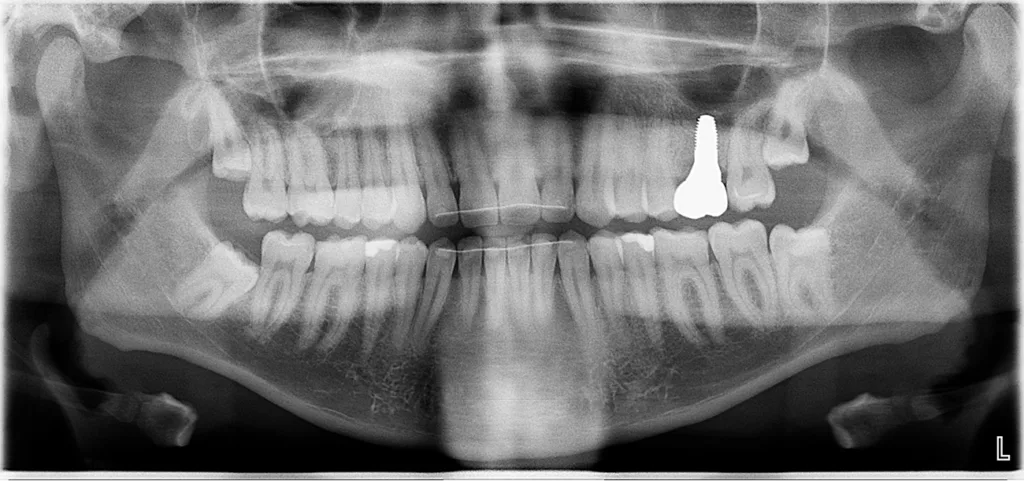

Abb. 2: Repräsentativer Fall von ABH Grad B Septus Typ II. a) Ansichten vor der Installation. Röntgenaufnahme der periapikalen Läsion an einem wurzelkanalbehandelten Molaren und klinische Ansicht der Typ-II-Socket nach der Extraktion. b) Die Ansichten nach der Installation zeigen das Implantat innerhalb des interradikulären Septums und das über dem Implantat platzierte A-PRF. c) Nachuntersuchungen nach 10 Tagen bzw. 2,1 Monaten. Die Röntgenaufnahme zeigt die Knochenbildung zwischen der Sinusmembran und dem apikalen Teil des Implantats. d) Jüngste Nachuntersuchung nach Einsetzen der Prothese.

Abb. 3: Repräsentativer Fall von Grad A Typ I. a) Präoperative Ansicht. Röntgenbild der periapikalen Läsion an einem wurzelkanalbehandelten Molaren. Die Höhe des Alveolarknochens zeigt Grad A an. b) Klinische und radiographische Ansicht der Implantatinsertion unter Verwendung einer Einheilscheibe mit großem Durchmesser (6×8 mm). A-PRF wurde um das Implantat und unter der Scheibe platziert. c) Nachuntersuchung nach 5,9 Monaten vor und nach der Zementierung und Aufbereitung. d) Jüngste Nachuntersuchung nach Einsetzen der Prothese

Abb. 4: Repräsentativer Fall von Grad A Typ III. a) Ansichten vor der Implantation. Röntgenbild der periapikalen Läsion an einem wurzelkanalbehandelten Molaren. b) Die Extraktionsalveole zeigt ein interradikuläres Septum vom Typ III (B).

Der Erfolg der Implantate wurde nach den Kriterien des Pisa-Konsensus von 2008 bewertet [9]. Alle Implantate wurden als Gruppe I mit einem durchschnittlichen marginalen Knochenverlust von –0,1775 + 0,68 mm nach 1 Jahr Implantation eingestuft, die einen Knochenverlust von < 2 mm und keine Empfindlichkeit, Beweglichkeit oder Exsudat aufwiesen.

Querschnittsbilder aus dem DVT zeigen eine hohe Genauigkeit und Zuverlässigkeit bei linearen Knochenmessungen im Zusammenhang mit der Implantatbehandlung [2]. Marginale Knochenniveaus wurden am Schnittpunkt zwischen der Längsachse des Implantats und der mesiodistalen Linie gemessen, die durch den größten krestalen Knochen auf jeder Seite des Implantats markiert ist und als Referenzpunkt für die Messung des Knochenverlusts bei Nachuntersuchungen dient. Trotz der begrenzten Anzahl von Implantaten und der Beschränkungen der Studie wurde eine Überlebensrate von 100% erreicht.